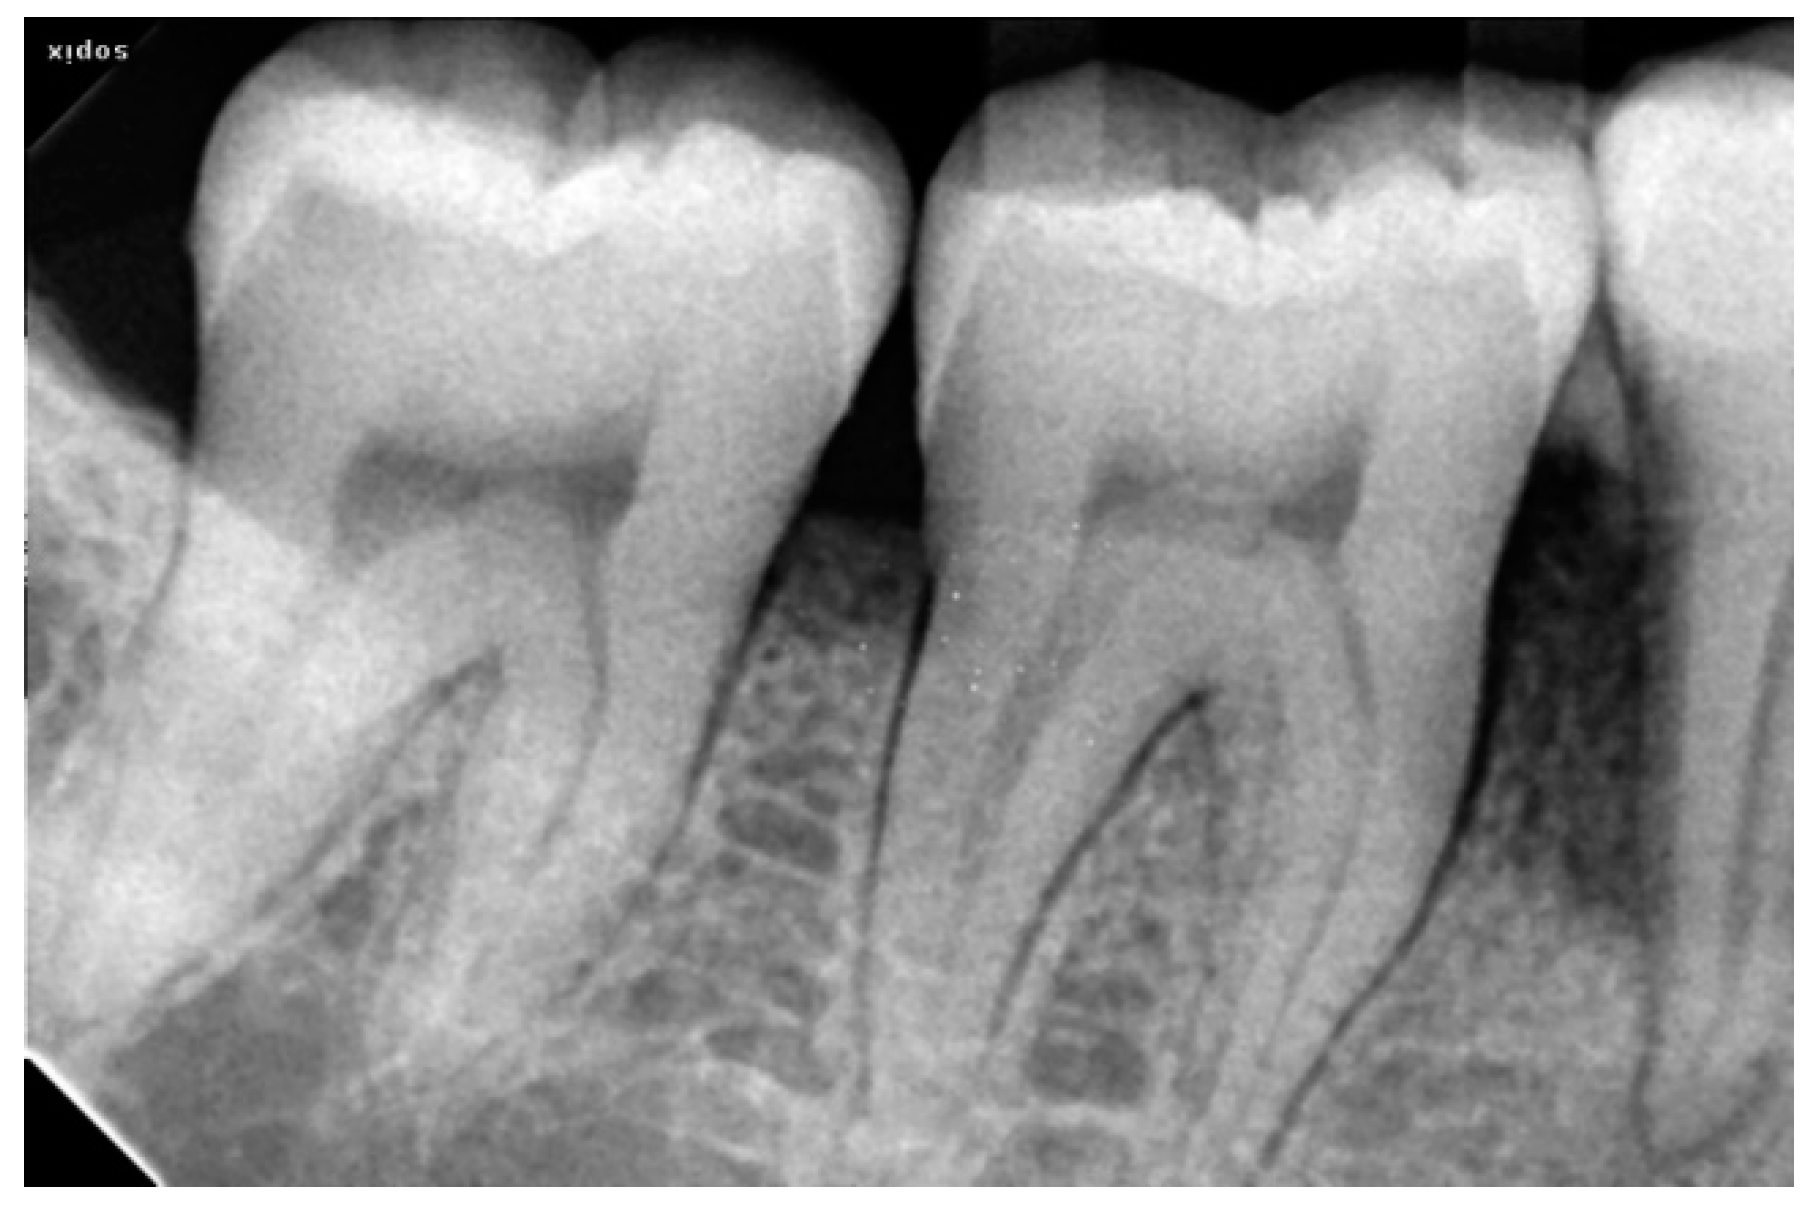

2.3. Radiographic Assessment

2.4. Surgical Procedure